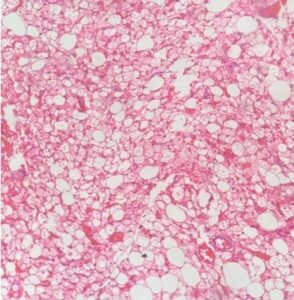

Grossly, the tumor had a yellowish lobular appearance. Microscopy revealed a lipomatous tumor composed predominantly of brown fat cells admixed with mature white fat cells. The brown fat cells contained round central nuclei and a multi vacuolated eosinophilic granular cytoplasm. A rich capillary network was present. Nuclear atypia, mitotic activity or lipoblasts were not seen. All these findings conclude that the lump is compatible with a Herbinoma. (Figure 1)

Figure 1- Hibernoma composed predominantly of brown fat cells. A rich capillary network is seen. (H&E stain x100)

Figure 2,3 : Brown fat cell composed of round central nuclei and a multivacuolated cytoplasm. (H&E stain x400)